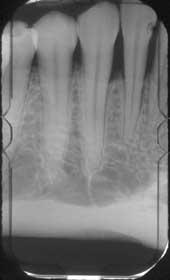

La imagen de arriba muestra los resultados de una angulación vertical incorrecta de la película, lo que resulta en la elongación de las raíces y la visualización inferior del borde de la mandíbula.